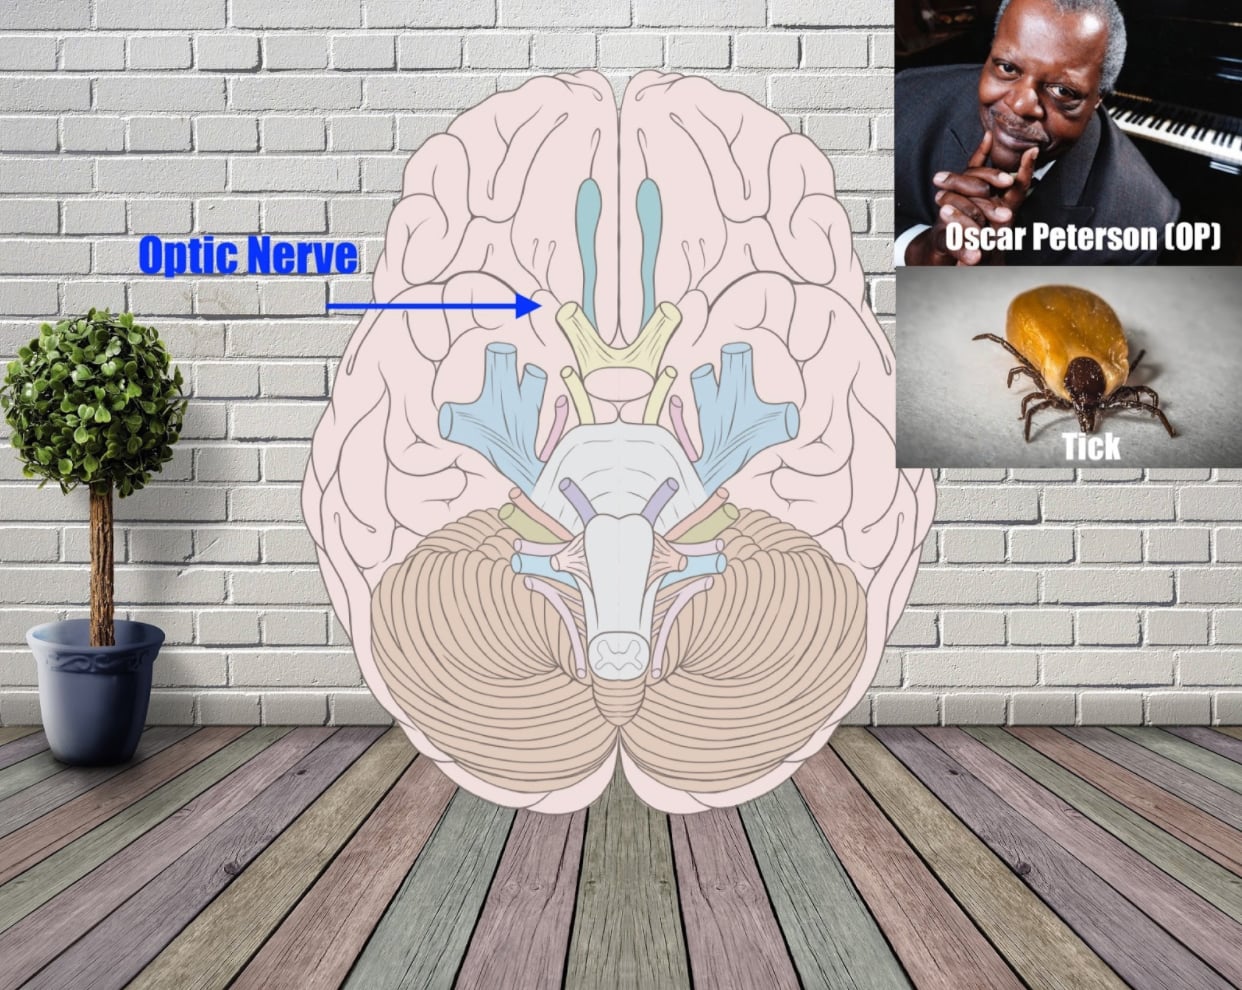

Optic Nerve (Sensory) – ‘OP’

The optic nerve carries visual information from the outside world into the brain.

Although not as clean as a name like “Oliver,” Oscar Peterson’s initials are OP. So are Om Puri and Otto Preminger. Or you could think of the Oregon Police.

Let’s say you go with Oscar Peterson. Maybe he’s playing a piano with keys made from ticks… And when he sees his piano keys in this condition, he freaks out and runs to the Oregon Police.

Yikes! That crazy image really is memorable!